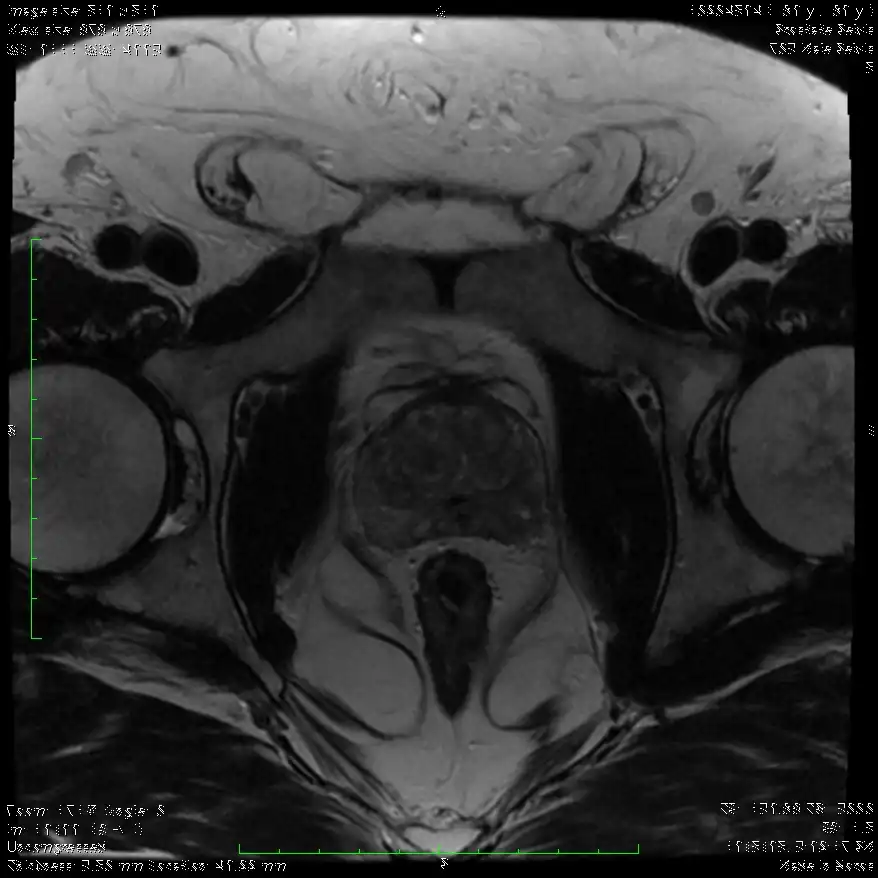

Η χρήση της πολυπαραμετρικής MRI στην διάγνωση του Καρκίνου του Προστάτη

Το 2018 ήταν η χρονιά που σε αρκετά έγκριτα περιοδικά (New England Journal of Medicine, European Urology, Lancet Oncology) δημοσιεύτηκαν μελέτες πάνω στο θέμα του καρκίνου του προστάτη. Οι μελέτες αυτές απέδειξαν την χρησιμότητα της πολυπαραμετρικής ΜRI στην αρχική διάγνωση. Κοινό συμπέρασμα σε όλες τις μελέτες ήταν η χρήση της πολυπαραμετρικής μαγνητικής τομογραφίας. Αυτό οδήγησε στην διάγνωση περισσότερων κλινικά σημαντικά καρκίνων.